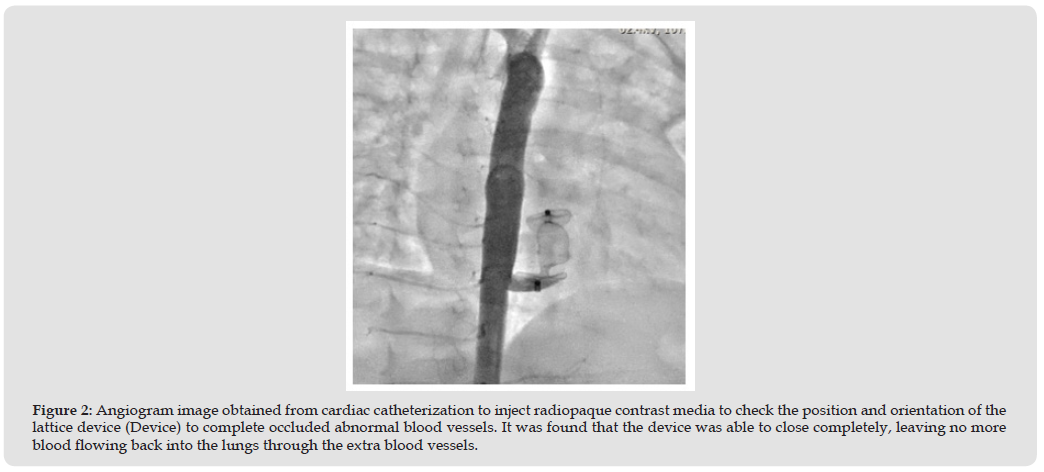

Although the standard tool for diagnosing pulmonary sequestration is computed tomography (CT) [6], The method of treatment for transcatheterization, angiography can be used to locate and confirm the lesion. (Figures 1A,1B & 2) However, both of the above methods are usually ordered after an initial Transthoracic echocardiography for detecting lesions and detecting concomitant pathologies [7], The standard view of echocardiography was including Parasternal view, Apical view, Subcostal view, and Suprasternal view. But the necessary view for diagnosing pulmonary sequestration are modified two chambers view and modified subcostal view (Figures 1 & 3).